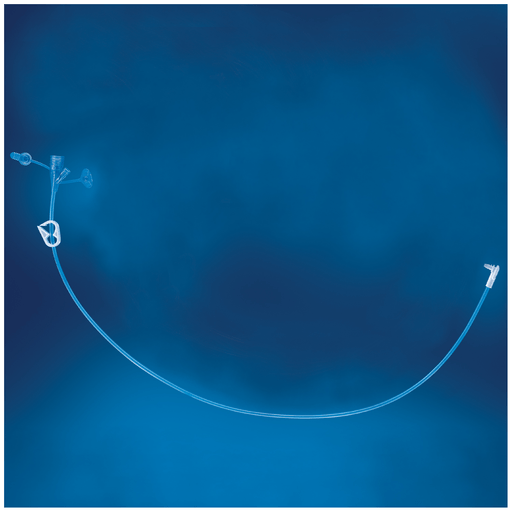

AVANOS MIC-KEY CONTINUOUS FEED EXTENSION - Extension Set, Secur-Lok, 24", Right Angle Connector, 2 Port "Y" & Clamp, 5/cs (Authorized Distributor Sub-Agreement Required - See Manufacturer Details Page) | Quantity - 1x CS

- Extension Set, Secur-Lok, 24", Right Angle Connector, 2 Port "Y" & Clamp, 5/cs (Authorized Distributor Sub-Agreement Required - See Manufacturer Details Page) Stock Item

- Extension Set, Secur-Lok, 24", Right Angle Connector, 2 Port "Y" & Clamp, 5/cs (Authorized Distributor Sub-Agreement Required - See Manufacturer Details Page) Stock Item